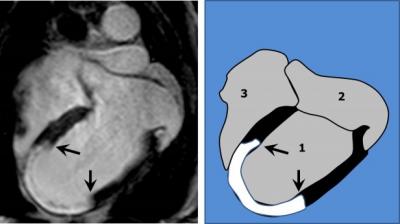

The efficacy of the intervention was evaluated by magnetic resonance imaging a week after the infarction. In an MRI protocol designed by the CNIC Imaging Unit (established in 2011 with the support of the Madrid regional government), the mass of necrotic heart tissue was measured in all patients. The results showed that patients who received metoprolol had much smaller infarcts than those who received the control treatment, and that this smaller infarct size was linked to greater heart contractility. As Dr. Fuster explains, "MRI is a unique tool for studying heart tissue that enables us to explore in exquisite detail heart function, necrosis, the state of the microcirculation and many other parameters that are critical in determining the post-infarction status of the myocardium". The MRI scans were analyzed at the central CNIC laboratory by cardiologists blinded to the treatment; the team of cardiologists at the CNIC are experts in this analysis, and most of them received their training from Dr. Fuster at the Mount Sinai Hospital in New York through a bilateral training agreement with the CNIC.